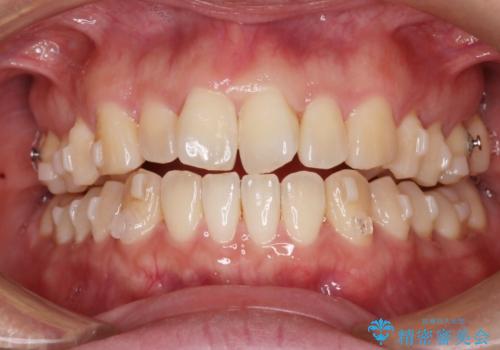

【インビザライン】前歯の捻れ気になる

- 上の前歯の捻れを主訴に来院されました。

前歯の捻れとがたつきを改善するために、IPR(歯と歯の間を削る処置)と歯列拡大をすることで歯並びを整えていく治療計画を立てました。

かみ合わせを整えるためにゴム掛けも行いながら、治療していきました。

患者様にマウスピースの使用とゴム掛けを頑張っていただいたおかげでリファイメント(マウスピースの再発注)も1回で終了することができました。